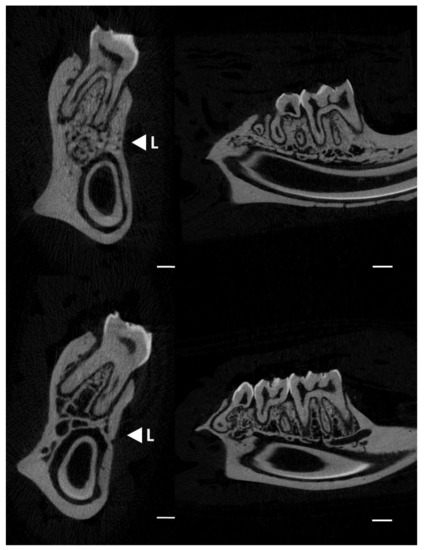

Figure 2 displays micro-CT images (transversal–left and sagittal–right sections) showing the changes in the trabecular bone distribution in the alveolar region of rat mandibles from the control and lead-exposed groups. Micro-CT images of the lead-exposed (Figure 2: upper images) group showed a marked loss of trabecular bone distribution compared with those of the control group (Figure 2: lower images).

Figure 2. Micro-CT images showing the changes in alveolar bone in rat mandibles (transversal and sagittal sections) in the control (upper images) and lead exposure (lower images) groups. <L; direction for the mechanical load (three-point bending test). Scale bars: 1 mm.

The bone micro-architectural parameters obtained by micro-CT analyses are reported in Table 1. Trabecular parameters in the alveolar bone from lead-exposed rats showed a significant decrease in the bone volume (BV; p = 0.019), ratio of bone volume/total volume tissue (BV/TV; p = 0.028), and bone mineral density (BMD; p = 0.014) compared with the control group. In addition, a significantly higher number of trabeculae was observed in the control group (Tb.N; p = 0.045), although no significant differences in trabecular separation and thickness or connectivity density were observed between groups.

Micro-CT analyses allow the study of morphological changes at the micro-architectural level in bone health and disease [32]. Here, we focused on the characterization of the trabecular organization in the alveolar bone region, as it constitutes the main structure in this specific non-weight bearing bone [1]. Moreover, alveolar bone is clinically quite important, as it represents the most metabolically active type of bone involved in dentition development [2]. The micro-CT results in the current research showed a significant decrease in the bone mineral density (BMD) and bone volume to tissue volume ratio (BV/TV) in the trabecular bone of lead-exposed rats compared with the control group. SEM images also confirmed this impairment in the trabecular structure of the alveolar bone. These observations showed higher porosity and a decrease in trabecular density in the lead-exposed group, particularly in the inter-radicular region of the mandibular molars. Previous studies showed the effect of lead exposure on decreased bone density in both cortical and trabecular bone in rat femurs [10,33]. These effects indicate a similar mechanism of bone maturation normally associated with osteoporosis [34,35]. In fact, the decrease of the trabecular microarchitecture characteristics in alveolar bone has been related to increased incidence of osteoporosis and risk of fractures [35,36,37]. Furthermore, the trabecular bone in the alveolar region showed a decrease in the number of trabeculae in the lead exposure group. Similar alterations have been reported in osteoporosis, in which a marked reduction of the trabecular bone volume, as well as a reduction in the thickness and number of trabecular, was observed [32,38]. The process of bone remodelling comprises a number of cellular events in which trabecular sites, due to their high surface-to-volume ratio, were more commonly affected by the dysregulation in bone turnover processes [39]. The alteration of the bone metabolism caused by lead exposure [6,40] may be related to the deterioration of the trabecular characteristics in alveolar bone, which resembles bone mineral loss [33]. Moreover, mineral alterations in the alveolar region are associated with a physiological disorder that can lead to a structural disorder with important mechanical implications.